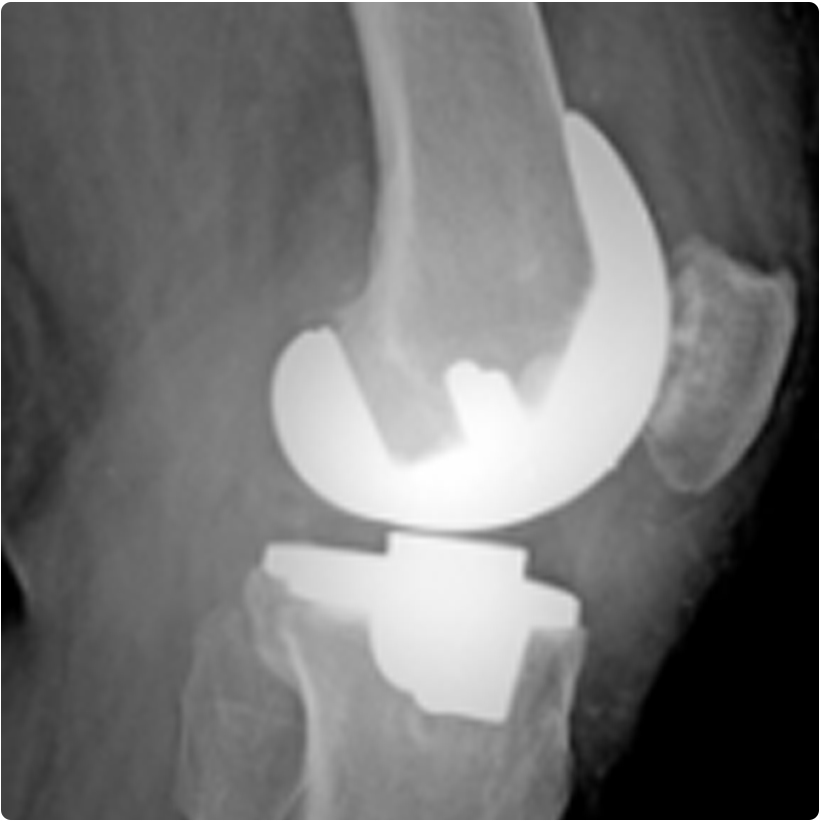

Protez iki metal parçadan ve aralarında yer alan bir plastik parçadan oluşur. Böylece normal diz eklem hareketlerini taklit eden metal bir eklem elde edilir.

Ayrıca hastanın dizinin sadece bir bölgesi bozulduğunda, özel bazı durumlarda kullanılabilen parsiyel (kısmi) diz protezi de vardır. Resimde diz ekleminde osteoartriti olan bir hastanın ameliyat öncesi ve total (tam) diz protezi uygulandıktan sonraki diz röntgen grafileri görülmektedir.